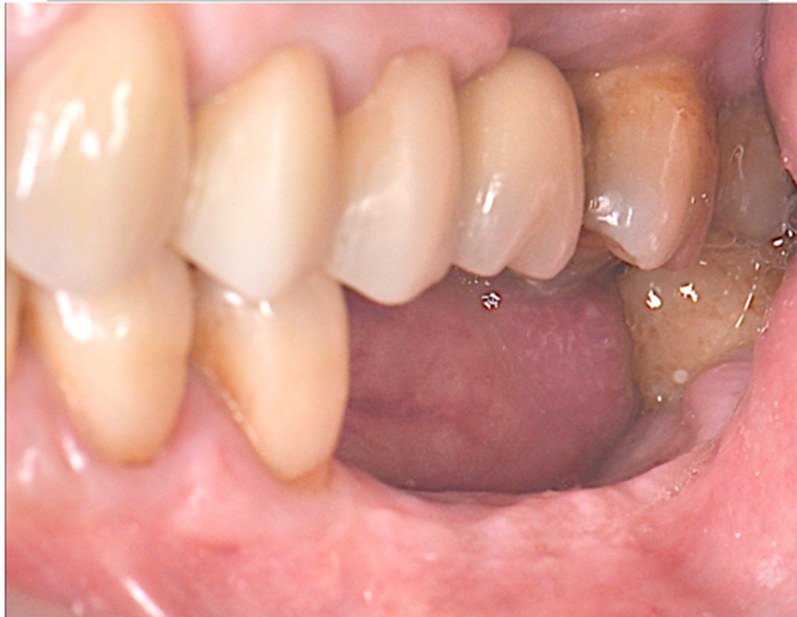

Selecionamos um caso clínico para ilustrar o fluxo de trabalho digital para Mini Cônico, onde foram planejadas duas coroas unidas nos elementos dentários 36 e 37 em zircônia monolítica, feitas sobre o pilar para próteses múltiplas.

Após o período de osseointegração dos implantes, a altura correta do transmucoso de cada Mini Cônico foi selecionada utilizando-se o medidor tunel check, e os pilares foram instalados com um torque de 20 Ncm. Sobre os componentes, foram confeccionados provisórios para a personalização do perfil de emergência.

Neste caso, a prótese múltipla foi desenhada sobre o Mini Cônico e as duas coroas foram fresadas unidas. Após a maquiagem final da zircônia monolítica, as coroas foram parafusadas sobre o Mini Cônico com um torque de 10 Ncm.

Podemos acompanhar o passo a passo das etapas, desde a seleção da altura do transmucoso do Mini Cônico até a instalação das coroas unidas no fluxo totalmente digital sem a utilização de componentes metálicos.